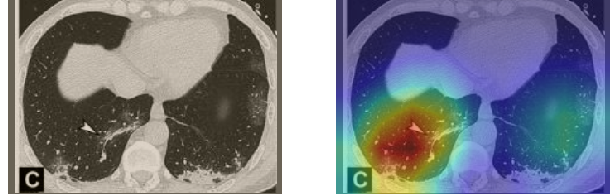

A wide variety of typical and atypical CT abnormalities have been reported for COVID-19 patients in various studies [58, 59]. So, we tested our models on external CT images extracted from these two publications as they feature typical findings of COVID-19 pneumonia marked by specialists. In order to make sure that not any of the extracted images are unintentionally included in our datasets, specifically the COVID19-CT dataset, we use the model trained on the SARS-CoV-2 dataset. First, the InceptionV3 model is employed to classify the extracted CT images. The model is able to correctly classify the given CT images as COVID-19. Second, in order to interpret the model’s generalization capabilities, we apply the Grad-CAM technique to visualize the regions of abnormalities that are considered. By assessing the different CT images in Figure 15, we can see that the model accurately localizes the disease-related regions. Even more interesting is the fact that the model ignores any specific marks in the images like letters and only localizes the COVID-19 related regions. These visual explanations show the success of our models to learn relevant, generic visual features related to COVID-19 and are capable to correctly classify CT images outside the datasets on which they are trained.

Figure 16 shows various CT scans where only one lung is visible. The CT scans are also extracted from the paper [58] and show different CT manifestations of COVID-19 pneumonia marked by red squares. The InceptionV3 model is capable to classify them correctly as COVID-19, although it is trained on CT scans where the entire lung is visible. Intriguingly, when applying Grad-CAM we can see that all regions of abnormalities are accurately localized. This also proves the potential of our model to detect COVID-19 abnormalities in CT images outside the dataset used for training.